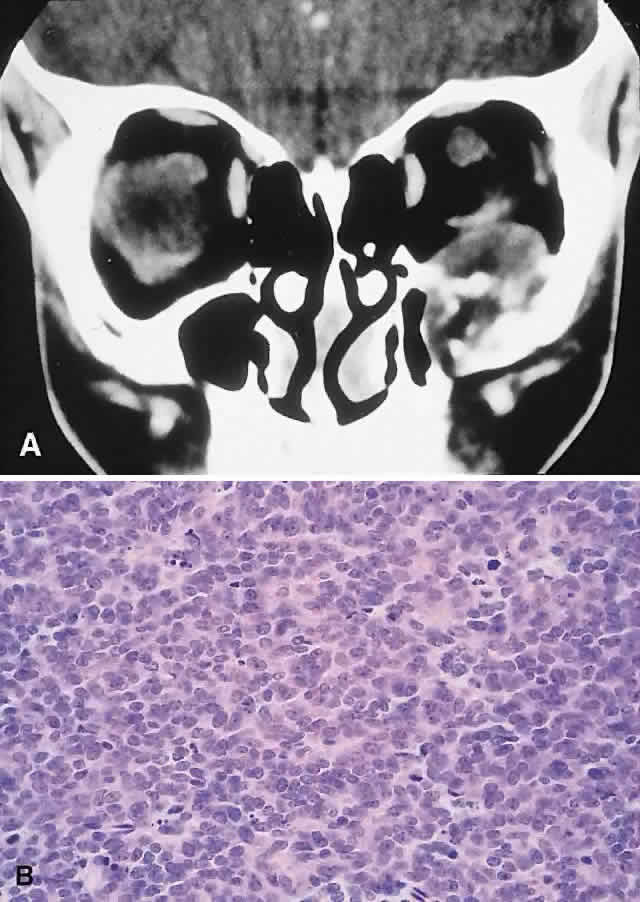

IMAGING. The CT appearance is of an expansile or permeating mass that shows mottled bone destruction (Fig. 11). There may be an associated soft tissue component.

Fig. 11. This 12-year-old boy experienced subacute left proptosis, vertical globe displacement, and lower lid edema. A. CT showed an expansile mass with mottled bone destruction of the orbital floor. B. Biopsy revealed a Ewing's sarcoma consisting of densely packed and mitotically active small round cells (hematoxylin-eosin, × 80).

HISTOPATHOLOGY. The tumor consists of firm, white tissue made up microscopically of sheets and clusters of uniform, small round cells. Cytoplasmic glycogen, as demonstrated by periodic acid-Schiff (PAS) positivity, is present in 90% of cases. Ultrastructurally, there is evidence of glycogen and a sparsity of organelles.18

The criteria for distinguishing Ewing's from neuroectodermal tumor of bone have not been well elucidated. In broad terms, however, Ewing's should not demonstrate signs of neuroectodermal differentiation on light or electron microscopy. Although they probably reflect different points in a spectrum of differentiation, the distinction continues to be made, in part because of the poorer prognosis of the neuroectodermal tumors of bone.136